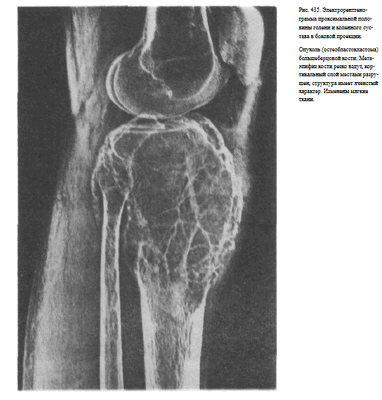

Информативность снимка. На рентгенограмме видны обе берцовые кости, их диафизы и метаэпифизы. В области диафизов костей хорошо различаются мозговая полость и корковое вещество. На снимках проксимальных двух третей голени, выполненных на пленке размером 24 х 30 см, отображены головка малоберцовой кости, частично или полностью метаэпифиз большеберцовой кости, а также иногда рентгеновская суставная щель коленного сустава (рис. 430, а). На снимках дистальных двух третей голени выявляются дистальные метаэпифизы большеберцовой и малоберцовой костей, иногда медиальная и латеральная лодыжки и рентгеновская суставная щель голеностопного сустава (рис. 430, б).

Информативность снимка. На снимке голени в боковой проекции в зависимости от размера используемой пленки должны быть отображены либо оба метаэпифиза берцовых костей, либо только проксимальный или дистальный метаэпифизы.

На снимке проксимальных двух третей голени (на пленке размером 24 х 30 см) раздельно определяются диафизы берцовых костей, а проксимальные метаэпифизы наслаиваются друг на друга. Видна бугристость большеберцовой кости (рис, 433, а).

На снимке дистальных двух третей голени также диафизы костей видны раздельно, а изображение метаэпифиза малоберцовой кости полностью суммируется с изображением метаэпифиза большеберцовой кости и таранной костью. Видна рентгеновская суставная щель голеностопного сустава